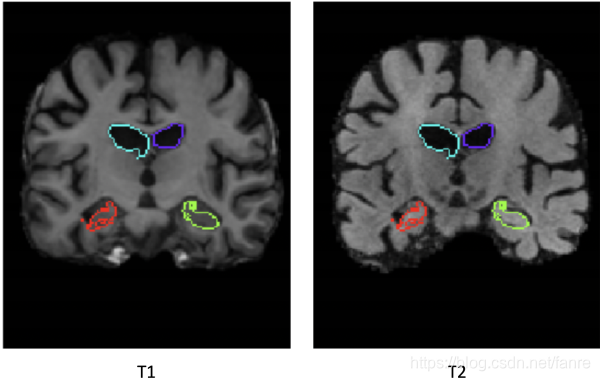

虽然我们的方法是无监督的,因此不需要分割,但我们使用分割精度作为一个代理来评估图像配准精度,因此我们需要对我们的T2 atlas进行分割,以评估我们的方法。T2扫描没有分割,但是所有的T1扫描都分割,所以我们取同一个病人的T1扫描并将其与T2扫描进行仿射配准。然后,我们用仿射变换warpT1扫描的segmentation ,得到T2扫描的segmentation。仿射关系通过ANTs-MI计算,使用传统的优化方法最大化MI来计算多模配准。由于两次扫描都来自同一对象,我们期望仿射配准会相当准确。因为我们没有T2 segmentations,所以没有办法对它进行评估,但是我们可以可视化resulting segmentation。从图4.1上看到脑室在T2上表现的非常好,并且海马体也覆盖的差不多。最后一步就是确保T2已经与所有的T1仿射对齐了,这样模型就变得比较容易训练。

图4.1 左边:原始的T1扫描和风格,仿射变换到T2扫描。右侧:T2扫描覆盖T1变换的分割。上面两个是脑室,下面两个是海马体。